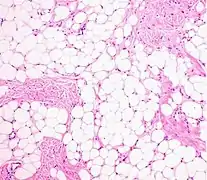

A lipoma is a benign tumor made of fat tissue.[1] They are generally soft to the touch, movable, and painless.[1] They usually occur just under the skin, but occasionally may be deeper.[1] Most are less than 5 cm (2.0 in) in size.[2] Common locations include upper back, shoulders, and abdomen.[4] It is possible to have a number of lipomas.[3]

The cause is generally unclear.[1] Risk factors include family history, obesity, and lack of exercise.[1][3] Diagnosis is typically based on a physical exam.[1] Occasionally medical imaging or tissue biopsy is used to confirm the diagnosis.[1]

A physical exam is typically the easiest way to diagnose it. Rarely, a tissue biopsy or imaging may be required. The imaging modality of choice is magnetic resonance imaging (MRI) because it has superior sensitivity of distinguishing it from liposarcoma as well as mapping the surrounding anatomy.[22]